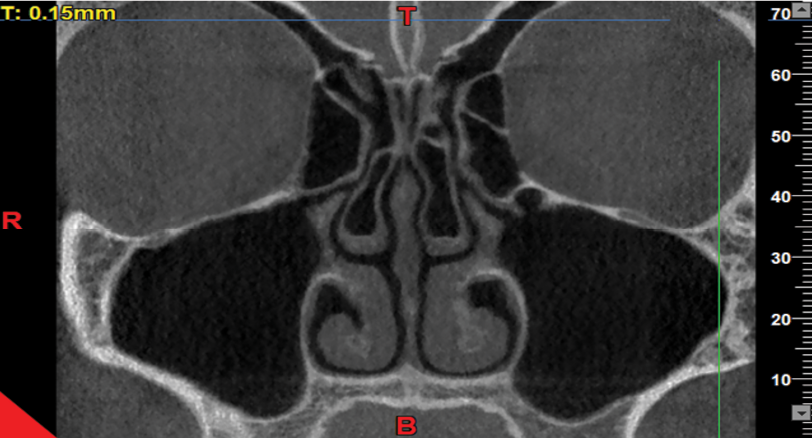

The axial, coronal, and sagittal views were used to assess the presence/absence of concha bullosa (Figure-1), and to measure the infundibulum length and ostium height (the most reliable and commonly used view to identify concha bullosa and make the measurements is the coronal view). The reviewed images visualized both the maxillary sinuses and the nasal cavity. Images with poor quality and those not visualizing the sinus floor, showing complete obstruction of the ostium, or lacking the middle concha were excluded. The patients’ age and gender, presence/absence of right and left concha, infundibulum length, and right and left ostium height were all recorded. The CBCT scans were evaluated by a board-certified oral and maxillofacial radiologist with 20 years of clinical experience. Subjectivity of the measurements was a source of bias in this study. To verify the reliability of the measurements, the intra-examiner reliability was calculated by repeating the measurements after a 3-month interval. The intraclass correlation coefficient was calculated to be 95%, indicating excellent intra-examiner reliability. To measure the dimensions of the drainage system, the infundibulum length and the ostium height were measured on both sides. For this purpose, the coronal view was scrolled to select the cross-section in which the uncinate process and the path of infundibulum and ostium were clearly visible, had an open path, and the largest values of the length and height were measured. The maximum length and height could be found on one or two different cross-sections. The infundibulum length was considered as the distance between the center of the ostium and the highest point of the uncinate process [3] (Figure-2). The ostium height was considered as the distance between the center of the ostium and the lowest point of the floor of the maxillary sinus [3]. To measure this variable, a line was drawn tangent to the lowest part of the sinus floor and parallel to the horizon. Next, a line was drawn perpendicular to the above-mentioned tangent line from the center of the ostium, and the obtained height was recorded (Figure-3).

Figure 1. CBCT showing pneumatization of the middle concha. Note the pneumatization and radiolucency in the middle concha, which were detected by scrolling the coronal view.